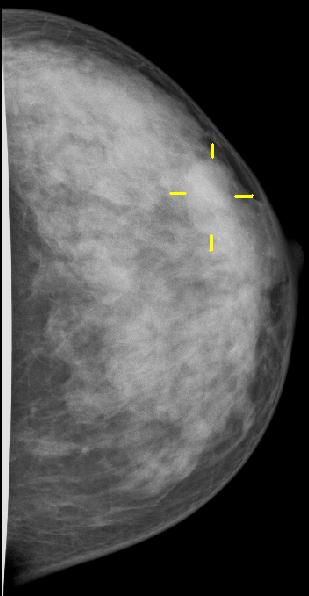

In der Mammographie einer dichten Brust ist das Karzinom kaum zu erkennen